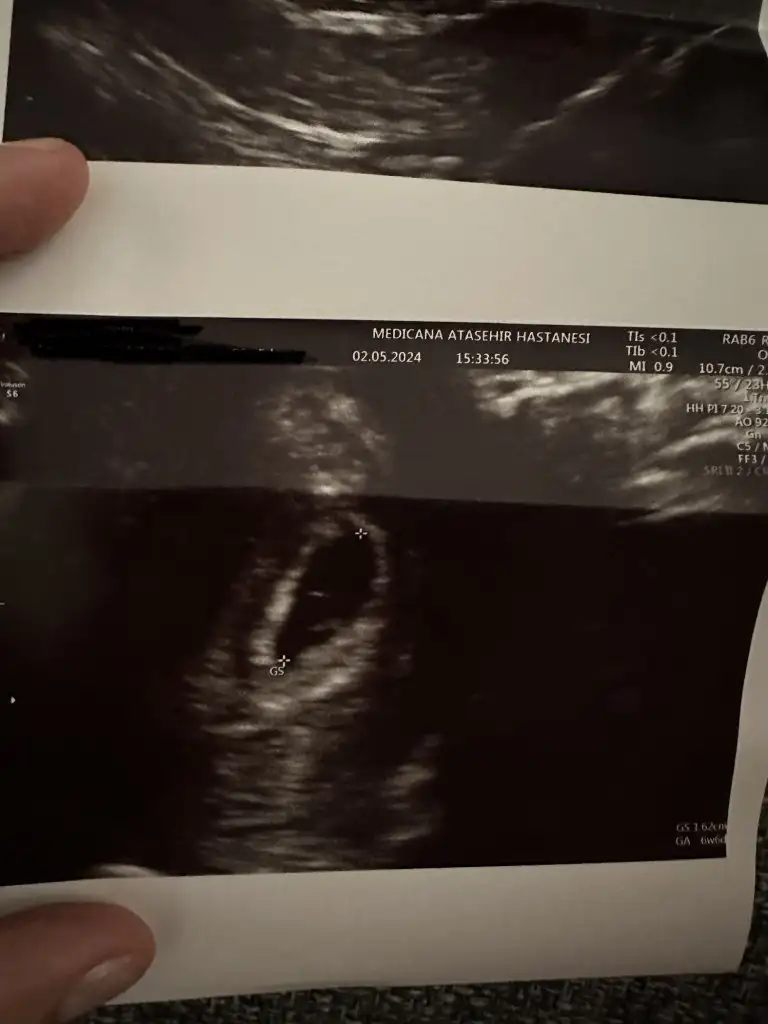

Ultrasonun kalitesi bile etkiliyor ya zamanı, görece daha eskiyse o bile duymanı engelleyebilir. Yolk sac vs görünmüştür belki ondan boş değildir demiştir kalbini ferah tutSelam kizlar ilk ultrasonuma 5+3 te girmistim kese gorunmustu dun 6+2 de tekrardan girdim tekrardan kese gorundu doktora cogu 6. Haftasinda kalp atisini duyuyo bende bebek henuz gorunmuyo bos gebelik mi acaba dedim hayir bos gebelik degik 5 6. Haftalarda kese gorunur 8. Haftada kalp atisi duyulur dedi ultrasonda biseyler gosterip bak yeni olusmaya basliyo dedi vajinal ultrason yapmadi ne oldugunu soramadin o an haftaya yine cagirdi benim durumumu yasayan var mi?